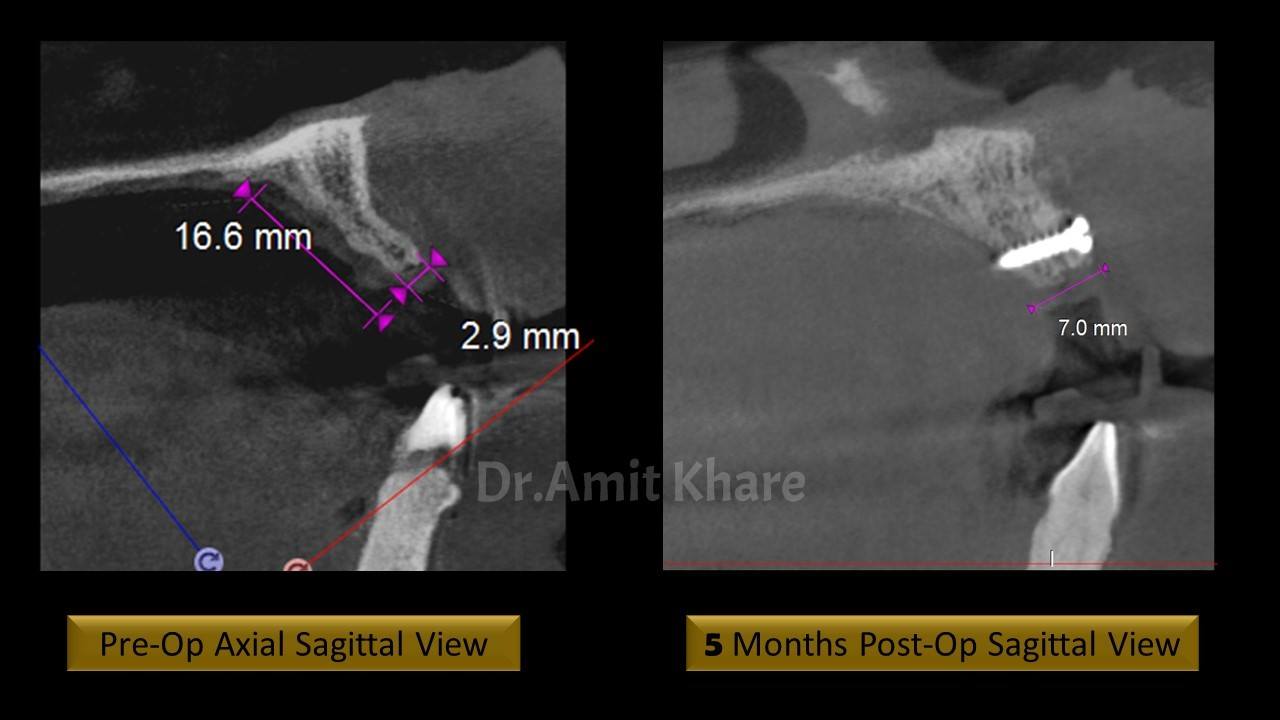

Clinical and Radiological investigation reveals deficient bone to receive an implant

Autogenous ‘Symphysis Block Graft’ was planned to regenerate the lost bone